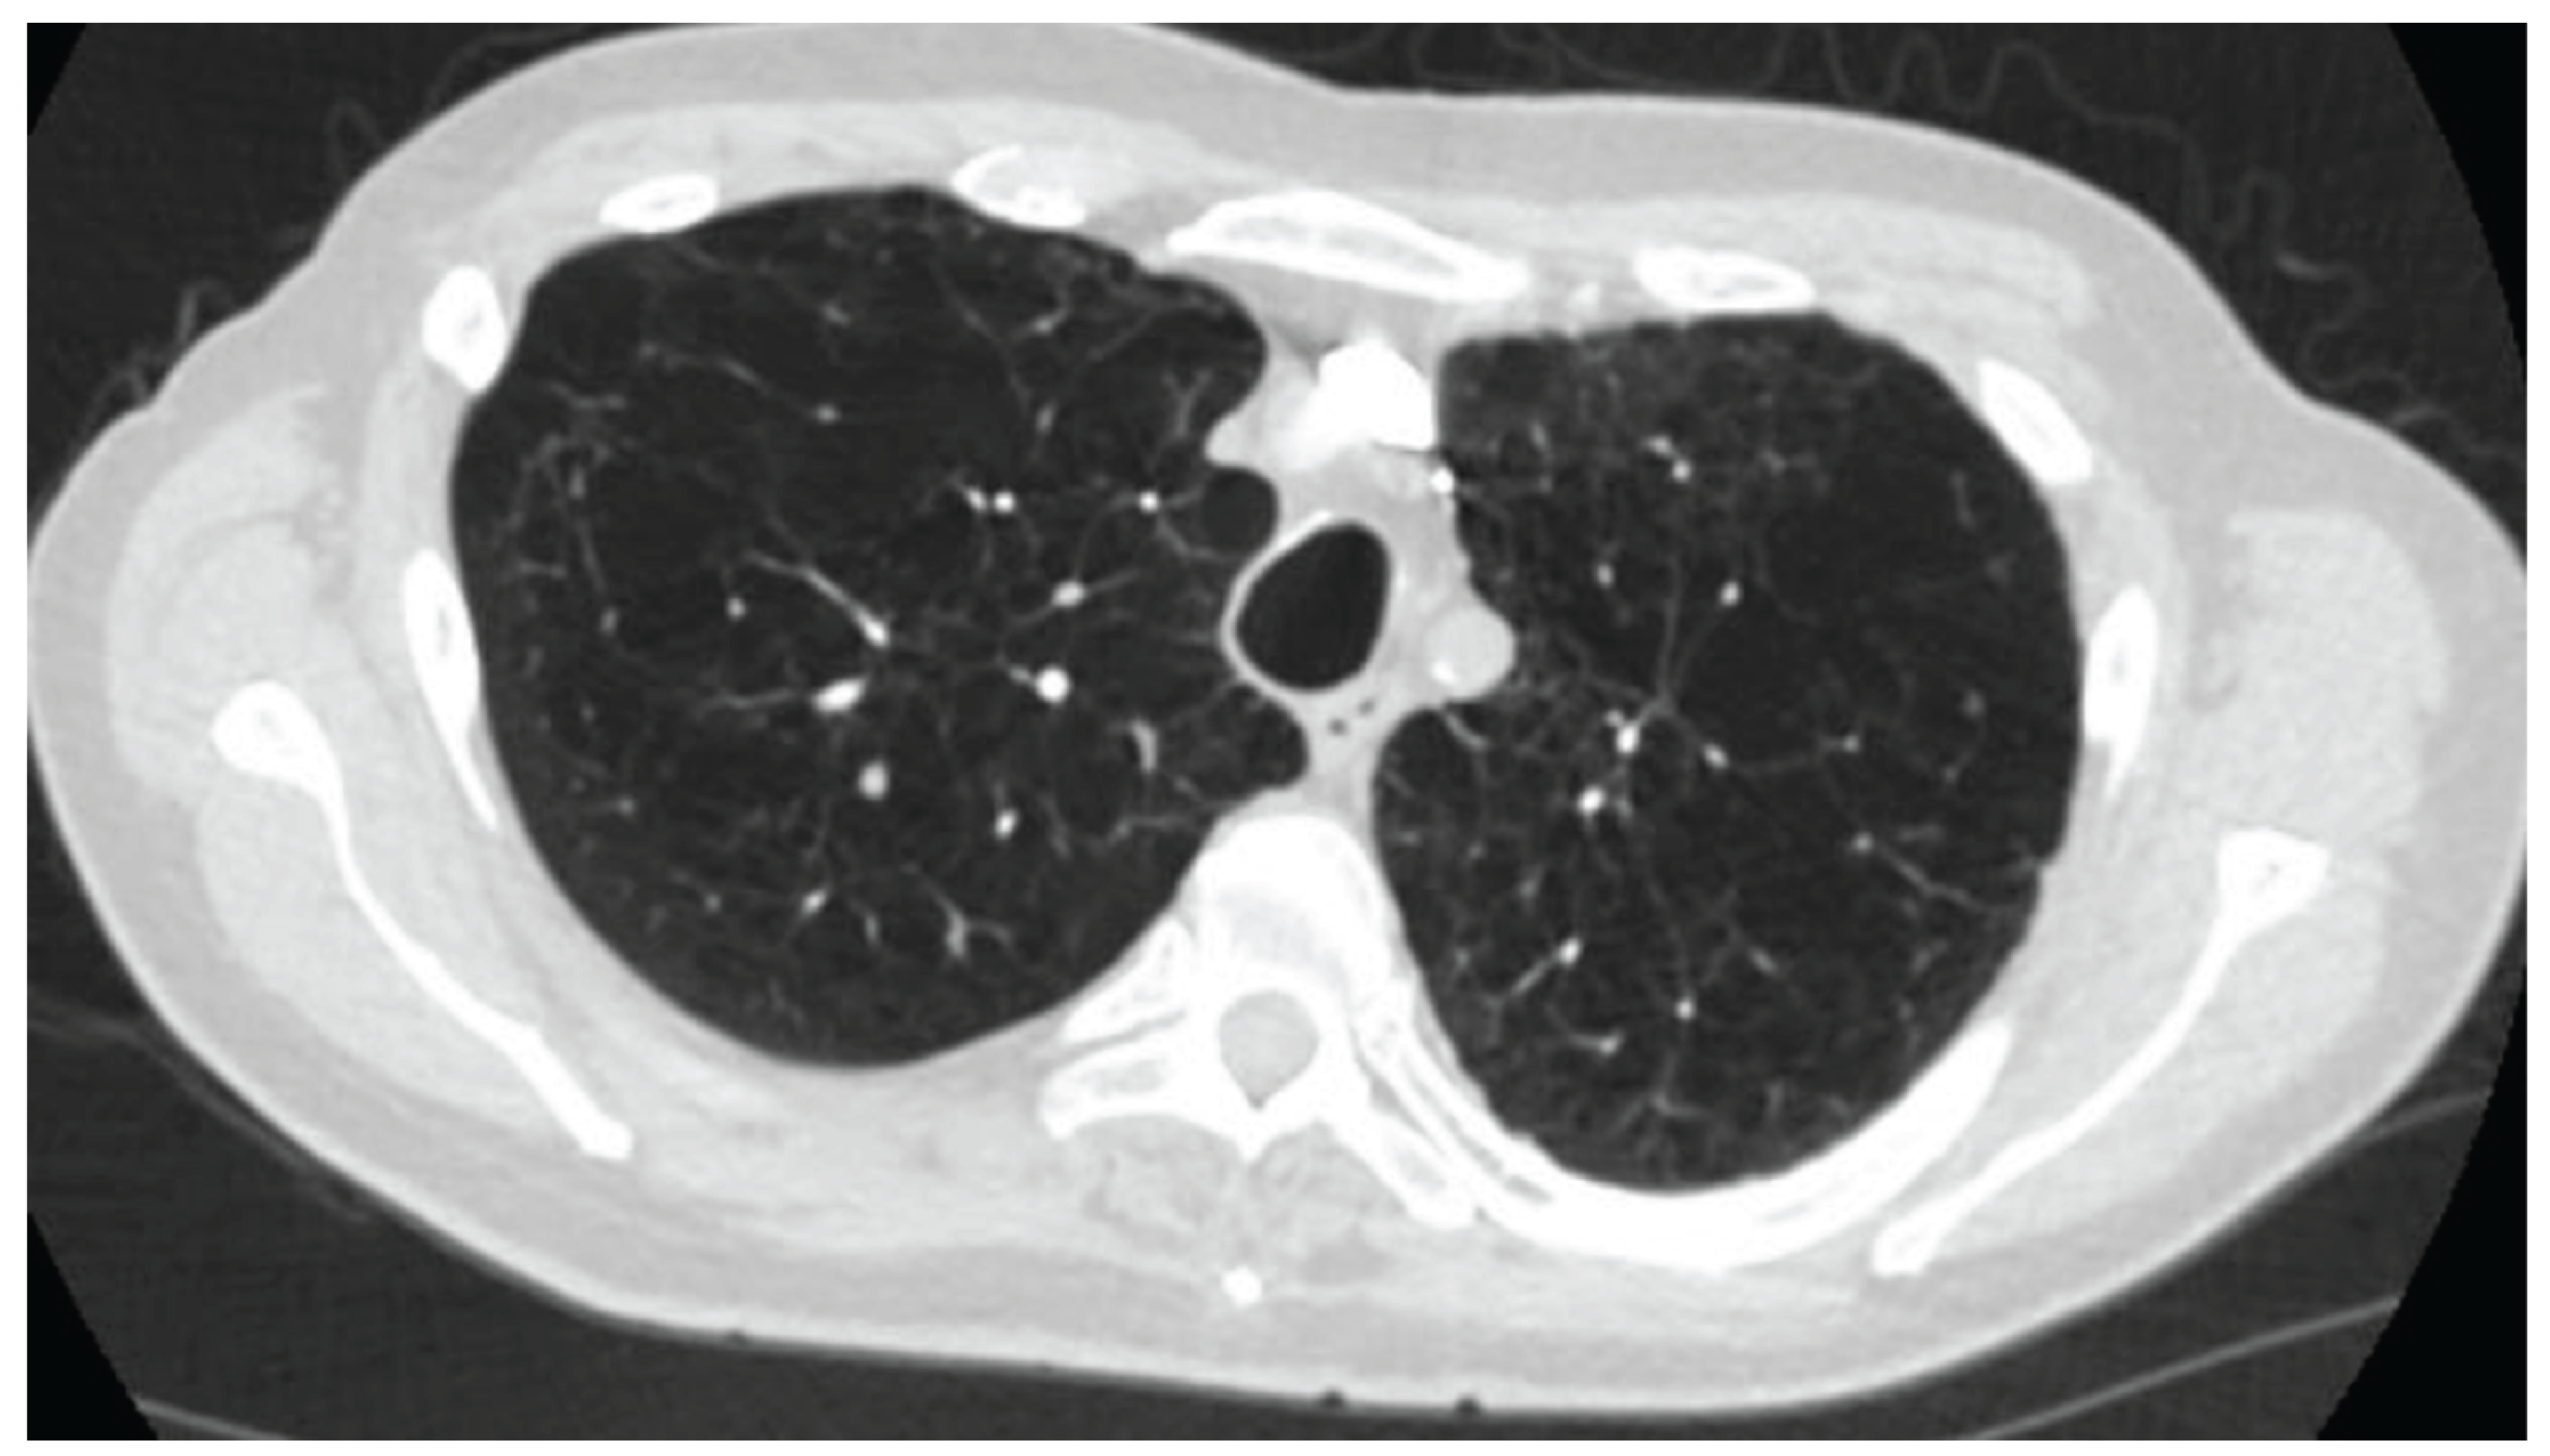

The cohort included 5 patients (mean age 76 years, 60% male, BMI 19.6, Charlson comorbidity index- 9.6). All were former heavy smokers (mean 47 pack-years) and had severe emphysema on imaging (See Figure 1 for a representative CT Chest of one the patients). Two out of five reported moderate exacerbations and another two severe exacerbations in the previous year. Clinical and radiologic evaluation suggested bronchitic phenotype in 3 out of 5 patients in additional to severe emphysema. Bronchitic phenotype was defined by the clinical history of persistent cough associated with mucus production for at-least 3 months in the previous 2 years. Baseline mMRC was 3.6, CAT 23, mean FEV1 (FEV: Forced Expiratory Volume) 33.4% predicted, and DLCO (Diffusion limited Carbon Monoxide) 29% predicted. The mean Hb was 14.6 gm/dl, absolute eosinophil count of 210/mm3. As a part of evaluation for worsening exertional dyspnea, all underwent echocardiography, which revealed pulmonary hypertension with a mean ePASP (estimated pulmonary artery systolic pressure) of 62.4 mm Hg and mean TAPSE (tricuspid annular plane systolic excursion) of 1.42 cm. BNP (Beta natriuretic peptide) averaged 90.4 pg/mL. The mean 6MWD at the time of initial evaluation was 224m. All were deemed not candidates for lung transplantation. See Table 1 for baseline characteristics.

Figure 1. Computer tomography of one of the patients, axial view, lung window at the level of trachea showing severe emphysema.